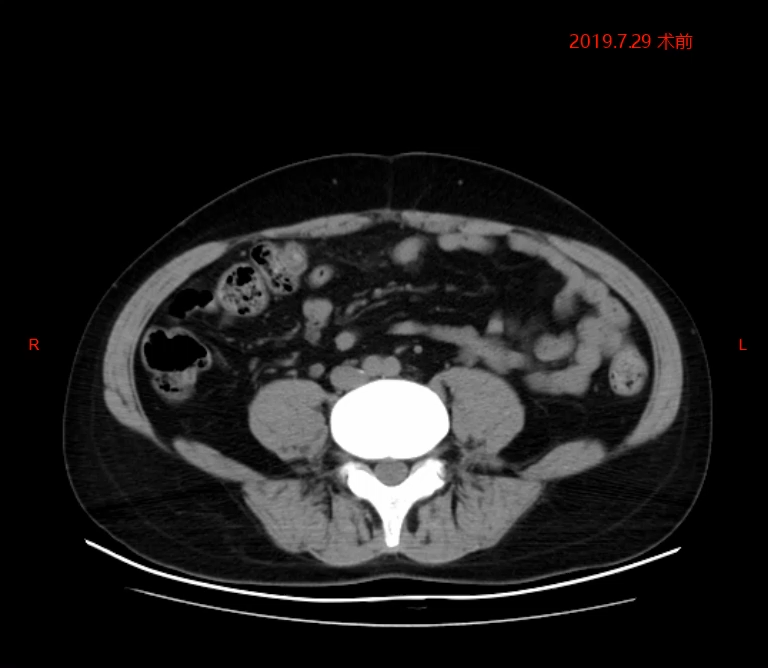

2019年7月术前检查

2019年7月术前检查